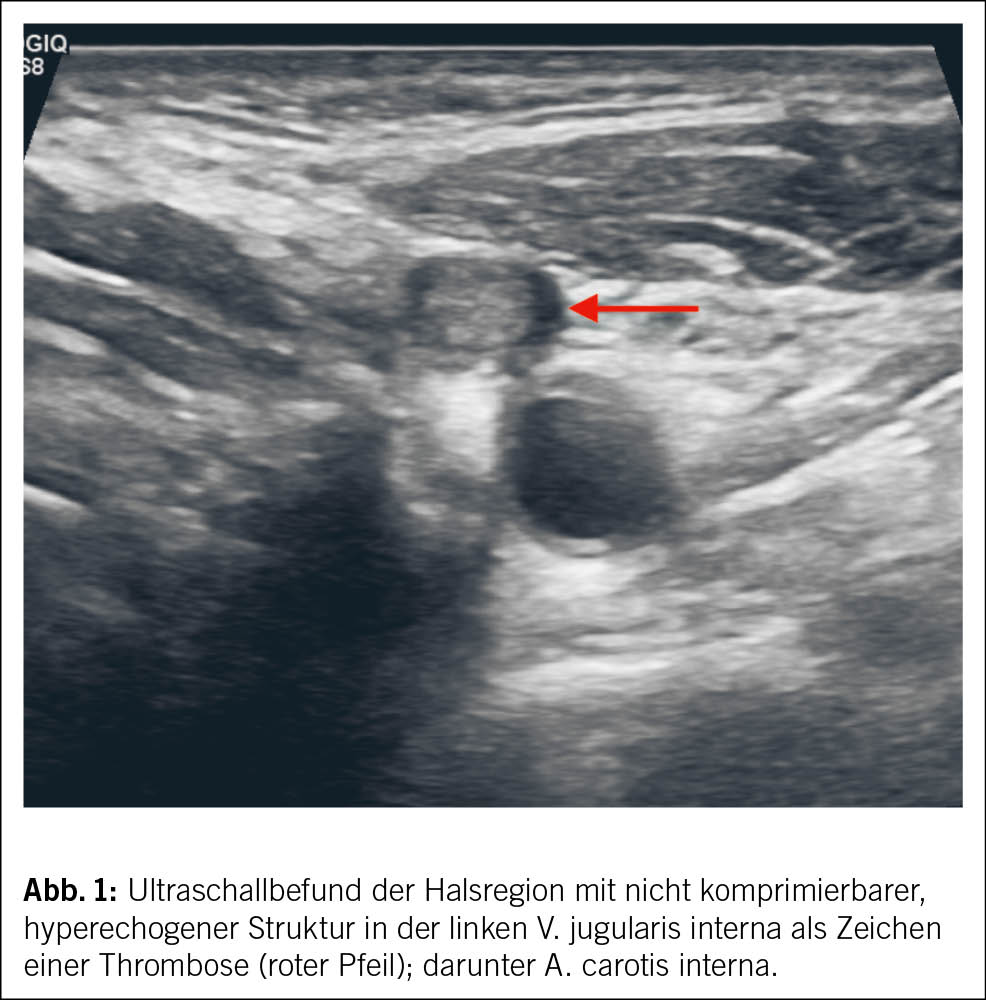

Zur weiteren Abklärung wurde eine Ultraschalluntersuchung der linken Halsregion durchgeführt. Hierbei zeigte sich im Bereich der linken Vena jugularis eine intravasale, echoreiche Struktur, die sich unter Druck des Schallkopfes nicht komprimieren liess (Abb. 1).